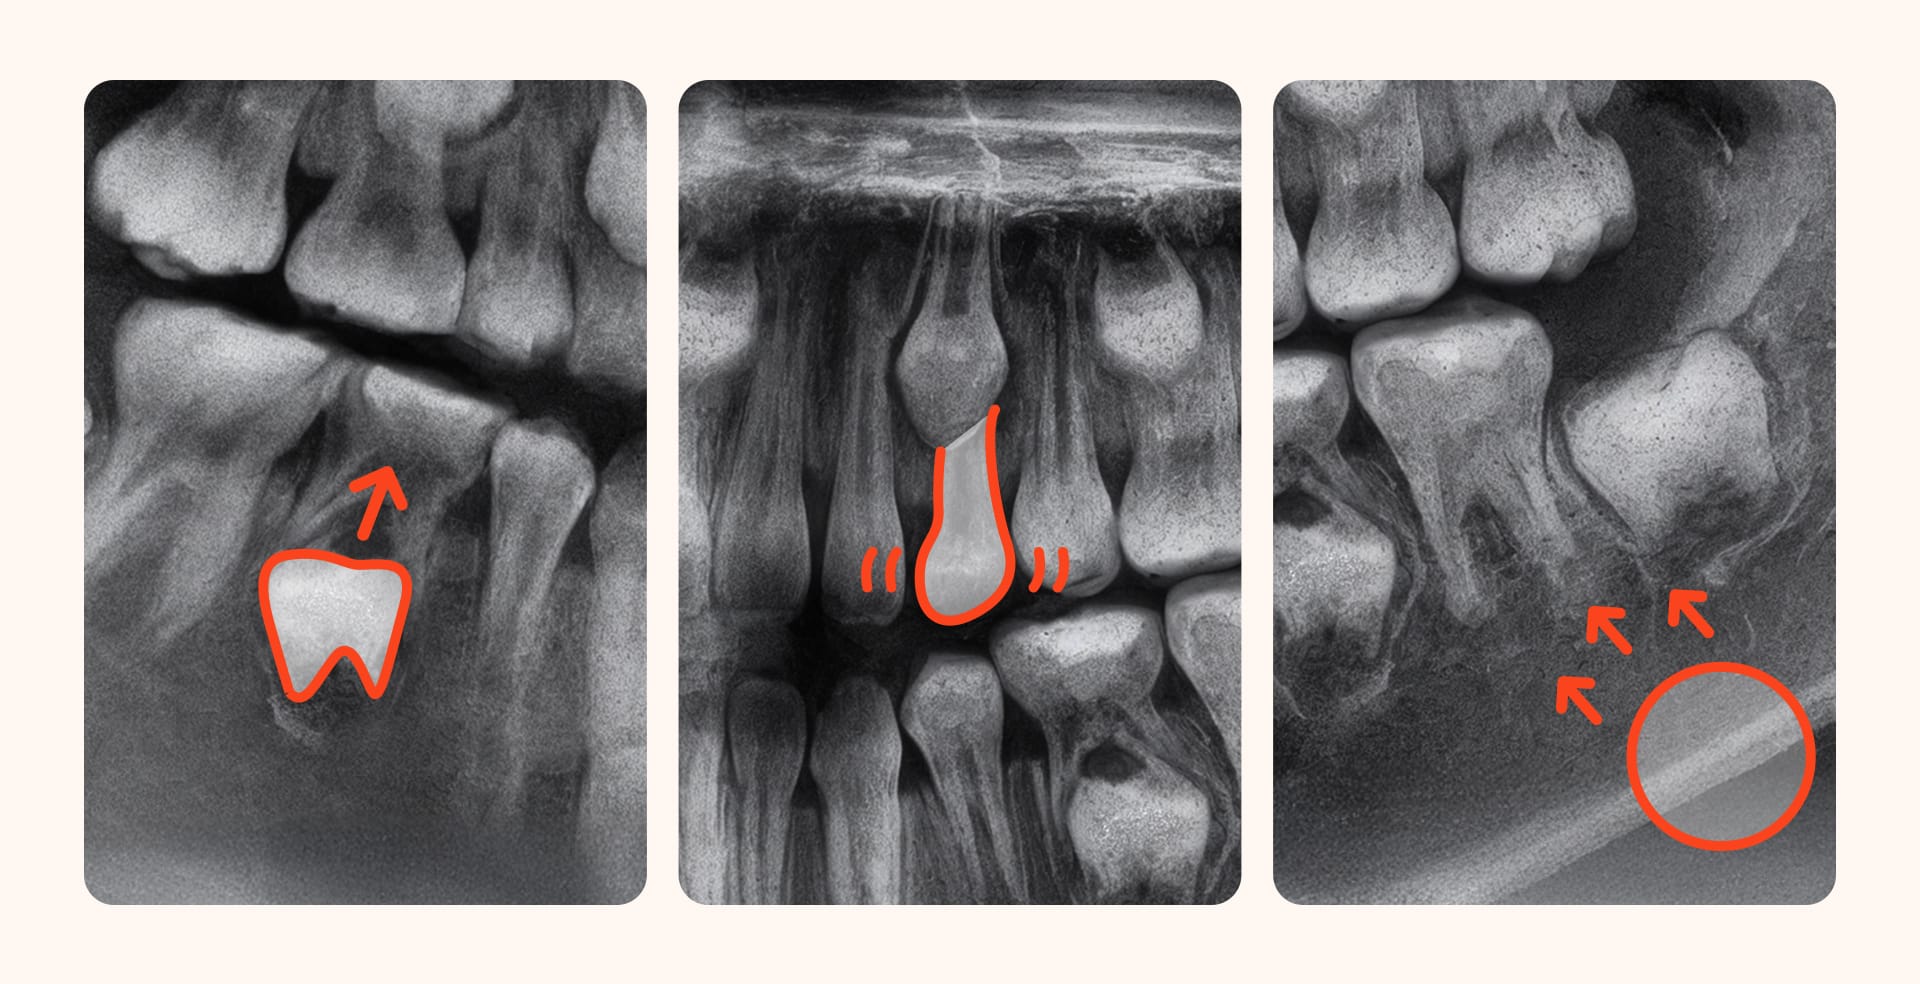

3. 대표적인 비수술 교정 사례

아이의 상태에 따라 필요한 교정 장치와 치료 계획은 달라지지만, 대부분의 성장기 부정교합은 비수술적 방법으로 치료가 가능합니다.

부모님들이 궁금해하실 만한 대표적인 부정교합 비수술 교정 사례를 중심으로 몇 가지 예시를 들어보겠습니다.

1) 개방교합 아동 – 가철식 장치

앞니가 벌어져 국수를 잘 끊지 못하거나 발음이 어눌한 경우입니다.

주로 혀를 내미는 습관이 원인일 수 있어, 가철식 장치와 함께 혀 습관을 교정하는 치료를 병행합니다.

장치를 꾸준히 착용하면 발음이 정상화되고, 벌어졌던 앞니가 다시 맞물려 기능을 회복할 수 있습니다.

2) 구호흡 아동 – 악궁 확장 장치

잠잘 때 입을 벌리고 자거나 얼굴이 길어지는 경향이 있다면 구호흡이 원인일 수 있습니다.

이 경우에는 좁은 윗턱을 넓혀주는 악궁 확장 장치를 사용합니다.

윗턱이 넓어지면 자연스럽게 숨길이 확보되어 혀가 제자리를 찾고, 입으로 숨 쉬던 습관이 코 호흡으로 개선되는 효과를 볼 수 있습니다.

3)돌출입 청소년 – 인비절라인 퍼스트

입술을 다물기 힘들어하거나 옆모습이 튀어나와 고민하는 경우가 많습니다.

인비절라인 퍼스트와 같은 어린이 투명교정 장치를 활용해 턱뼈의 성장을 유도하며 치아 배열을 바르게 잡을 수 있습니다.

꾸준한 장치 착용으로 돌출입이 개선되어 외모와 자신감까지 회복할 수 있습니다.